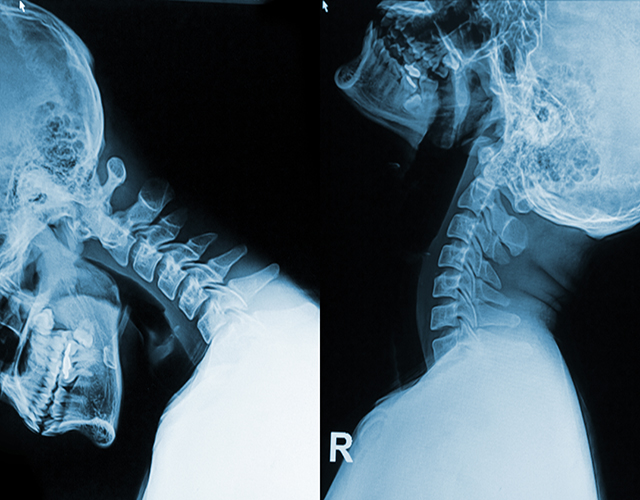

“醫(yī)生,頸椎反弓是怎么回事?還能不能恢復(fù)呀?” 門診的時(shí)候,有不少患者拿著頸椎X線片來詢問。

頸椎反弓是頸椎病最為常見的病理基礎(chǔ)。一般來說,人的頸椎是呈“C”形生理彎曲的。要是沒有這種生理彎曲了,甚至是朝著相反的方向彎曲,這就是頸椎反弓。